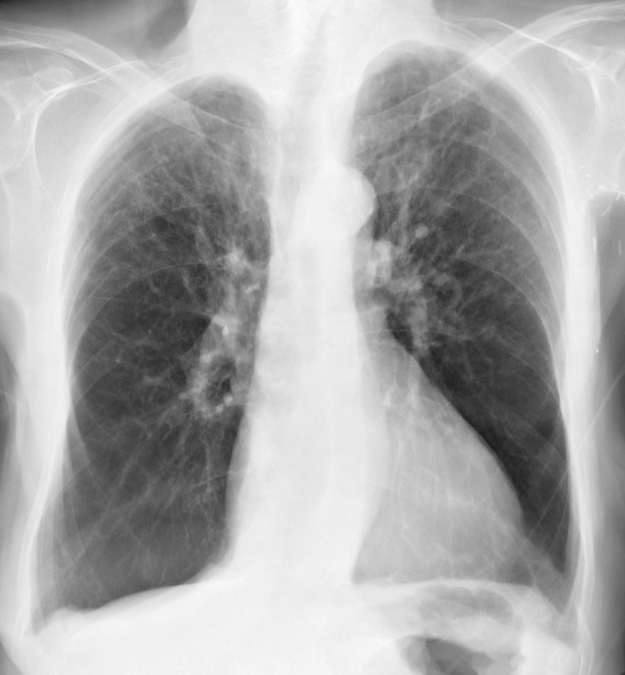

Gallery COPD alpha 1 antitrypsin

alpha 1 antitrypsin